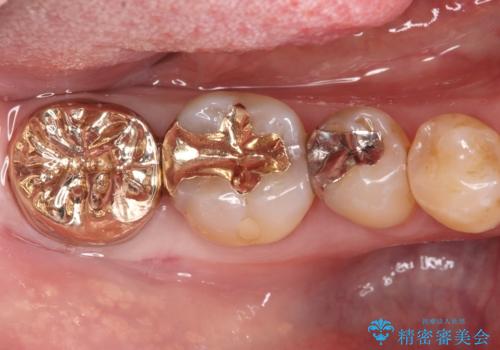

欠けた奥歯の強度を向上!PGAクラウンで安心の咬み心地を再建

- 以前治療した右下7番(奥歯)のインレー(詰め物)が欠けてしまったことを主訴にご来院されました。診査の結果、残っている歯質が少なく、通常の詰め物では再び歯が割れてしまう破折リスクが高いと診断しました。このリスクを回避し、強い咬合力に耐えられるよう、歯全体を覆うクラウン(被せ物)による修復を提案。素材には、強度と適合性に優れたPGA(白金加金)クラウンを選択し、長期的に安定した奥歯の機能回復を目指しました。

治療ではまず、欠けた部分を修復し、歯全体を均一に形成しました。その後、PGA(白金加金)クラウンを作製・装着しました。

PGAクラウンは、金(Gold)を主成分とする合金でできており、非常に優れた特性を持っています。

強度: 非常に高い強度を持つため、奥歯の強い咬合力にも耐え、歯の破折を効果的に防ぎます。

適合性: 歯への適合性が非常に高く、精密に隙間なく装着できるため、被せ物の下からの二次的な虫歯のリスクを最小限に抑えられます。

この治療により、欠けてしまった歯の構造的な弱点が解消され、患者様は硬いものでもしっかりと噛める、安心で機能的な奥歯を取り戻すことができました。